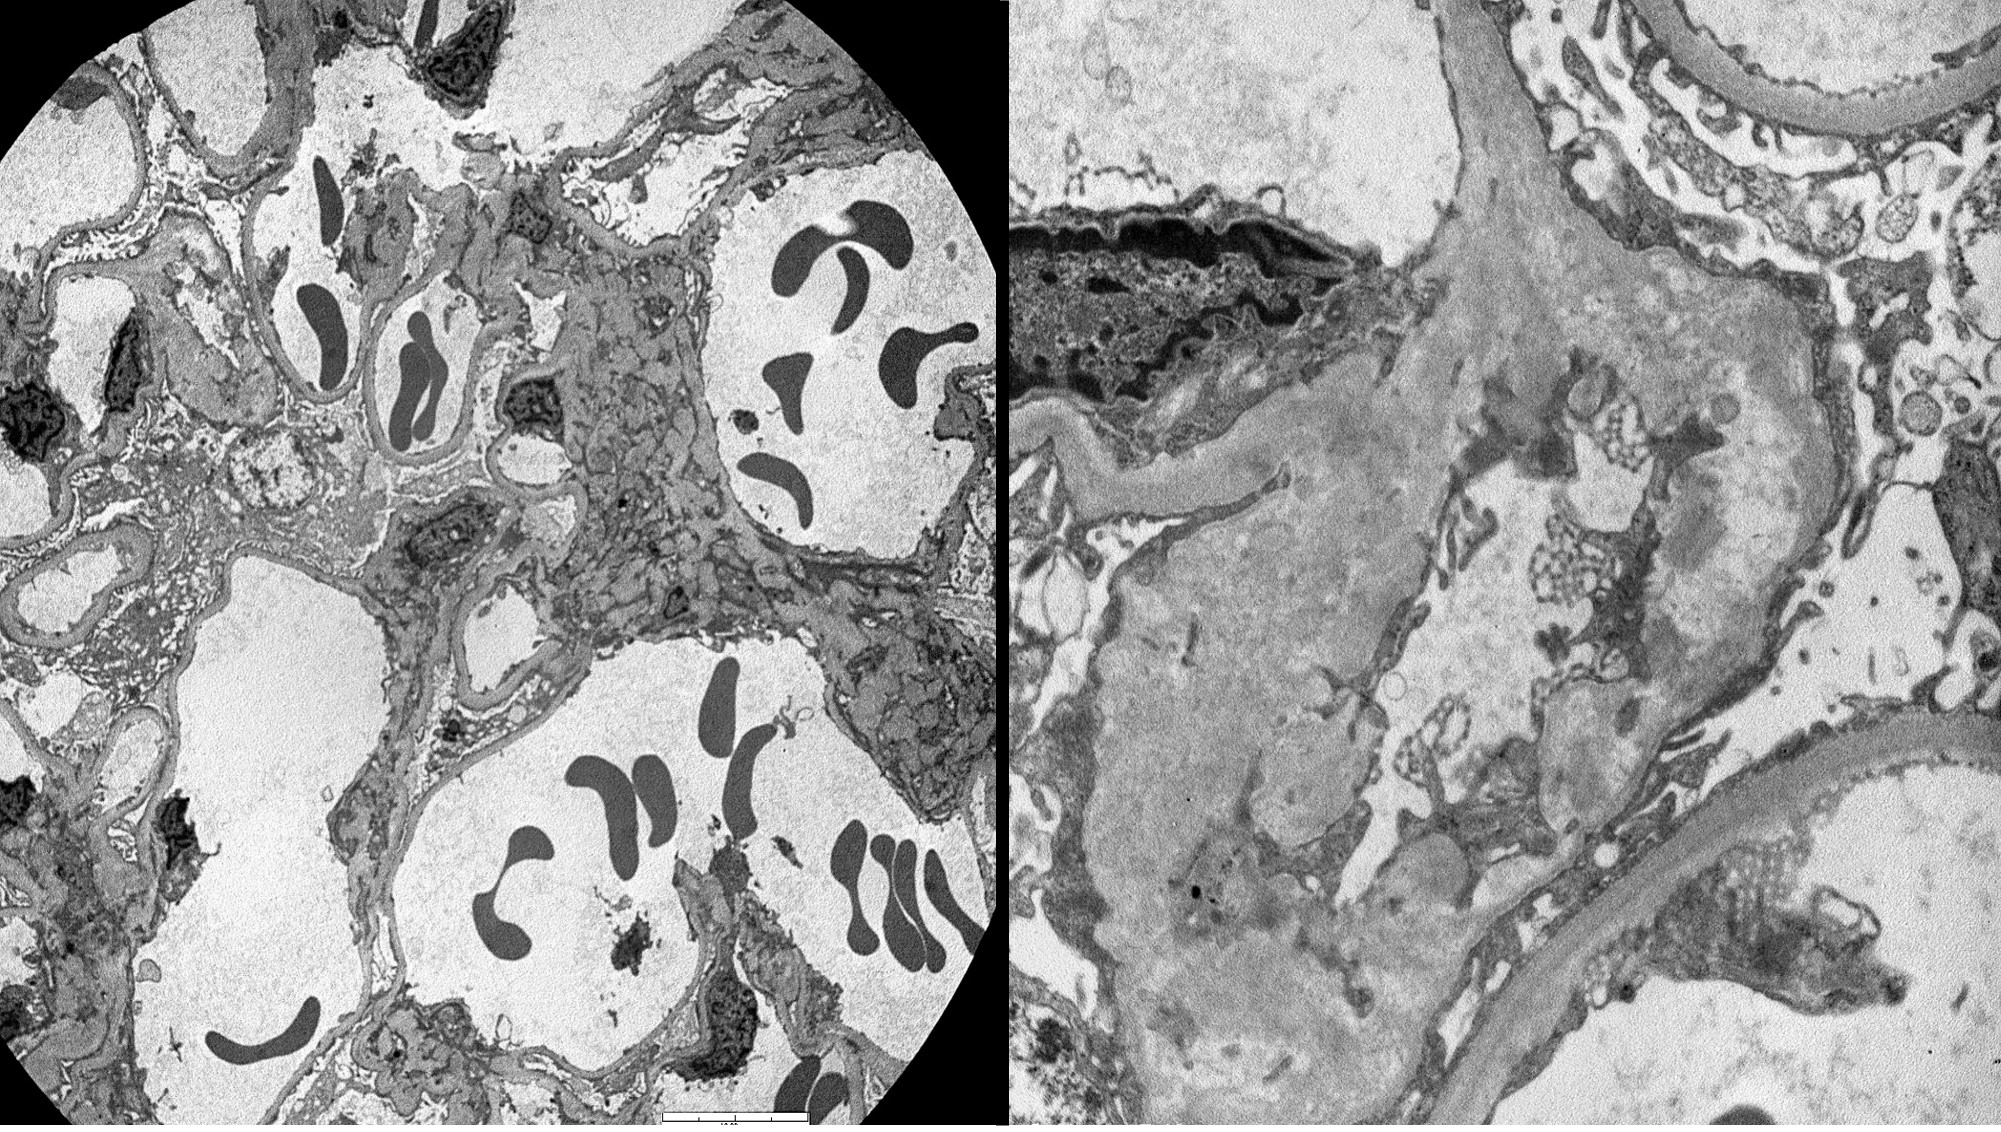

A 28 year old male presents with gross hematuria after a trip abroad. Cystoscopy and...